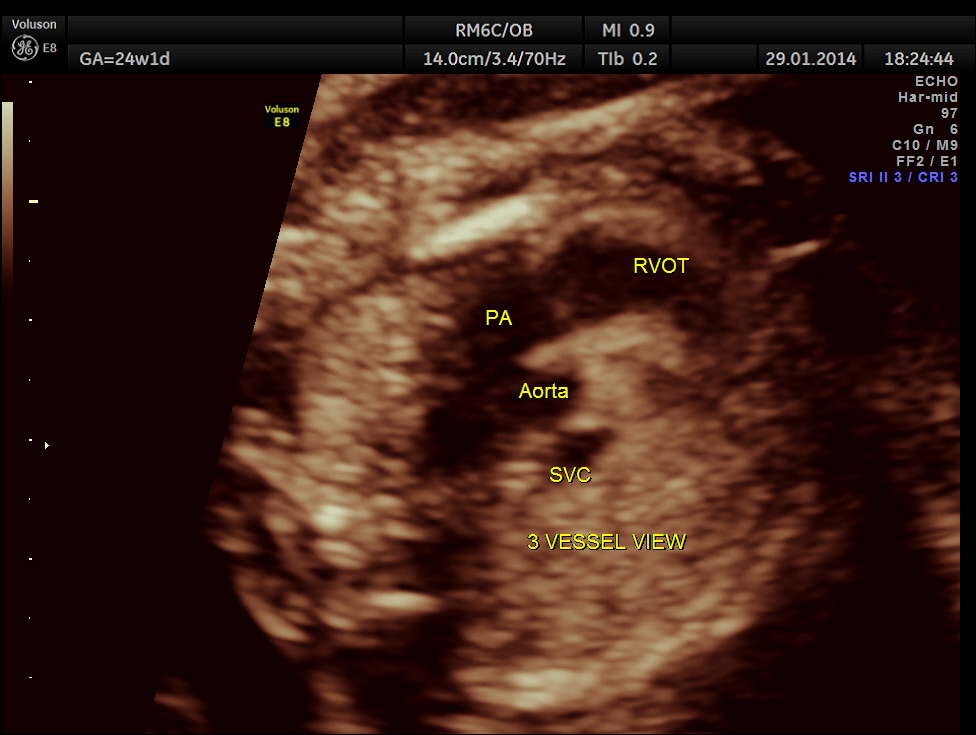

The 3 vessel trachea view depicts great vessel disproportion. Pulmonary artery is bigger than aorta .

A normal 3 vessel view and 4 chamber view are given below.